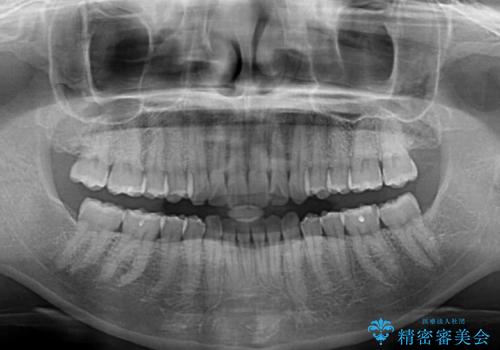

インビザライン矯正で前歯のデコボコを改善

- 前歯のデコボコを気にして来院された患者様です。

目立たないことを最優先にしたいとのことで、デコボコは軽度であったことから、インビザラインにて矯正治療を行うこととしました。

骨格的に下顎骨が左にずれており、上下の正中一致は困難ではありましたが、IPR(歯と歯の間を削る)や後方への移動など組み合わせて、できる限り改善しました。

インビザラインはマウスピースを外している時間が長いと、長期間使用しても前歯のデコボコはあまり改善されません。こちらの患者様は治療期間が長くなり、装着時間が短くなってしまったことで、気になる部分の改善により長期間を要するようになってしまいました。